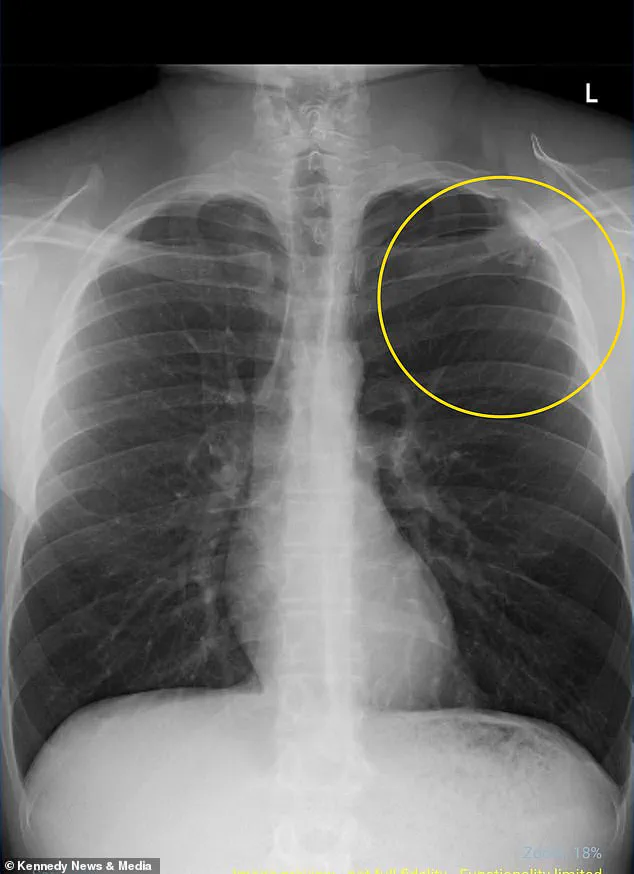

Rushed to the hospital, doctors diagnosed him with a partially collapsed lung, a condition medically termed pneumothorax.

This occurs when air leaks into the chest cavity, creating pressure that causes the lung to collapse.

An x-ray scan revealed that his left lung had collapsed by 10 percent, a minor collapse by medical standards, but one that required immediate intervention.

Pain medication and supplemental oxygen, along with an overnight hospital stay, allowed him to recover fully.